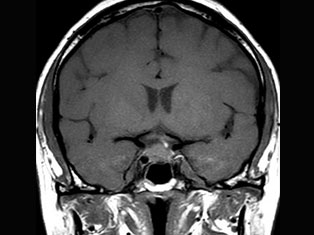

Brain Tumors

A brain tumor is a mass or growth of abnormal cells in your brain. Many different types of brain tumors exist. Some brain tumors are noncancerous (benign), and some brain tumors are cancerous (malignant).